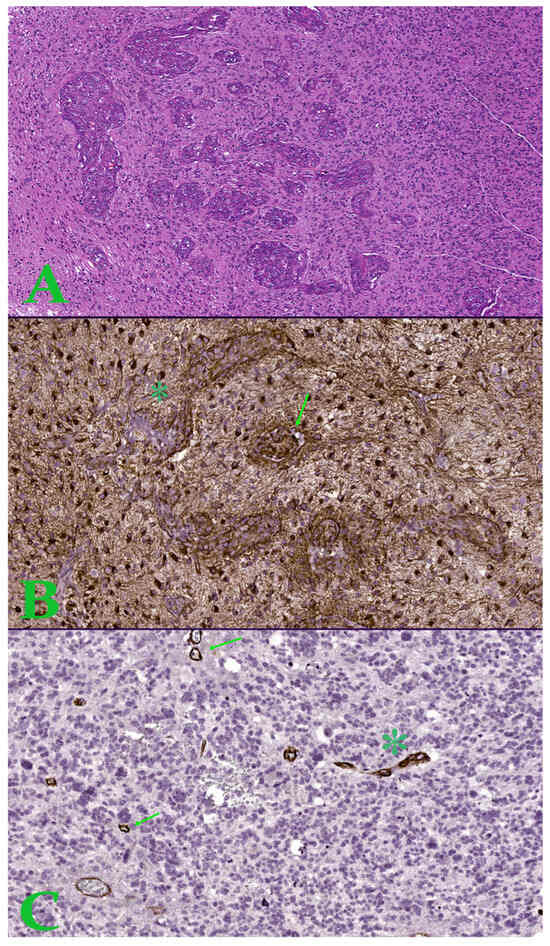

Association of a CD44s-v5-v6 Null Phenotype with Advanced Stage Cholangiocarcinoma: A Preliminary Study

Background/Objectives: Cholangiocarcinoma (CCA) is an aggressive malignancy with a poor prognosis, creating an urgent need for novel biomarkers to improve risk stratification. The prognostic significance of the transmembrane glycoprotein CD44 and its isoforms (CD44s, v5, v6) in CCA remains controversial. This preliminary [...] Read more.

Background/Objectives: Cholangiocarcinoma (CCA) is an aggressive malignancy with a poor prognosis, creating an urgent need for novel biomarkers to improve risk stratification. The prognostic significance of the transmembrane glycoprotein CD44 and its isoforms (CD44s, v5, v6) in CCA remains controversial. This preliminary study aimed to investigate whether the combined loss of these isoforms could serve as a distinct prognostic indicator. Methods: We evaluated the expression of CD44s, CD44v5, and CD44v6 via immunohistochemistry on a retrospective cohort of 61 paraffin-embedded CCA patient tissue blocks from Ramathibodi Hospital, Bangkok, Thailand. Expression levels were correlated with clinicopathological parameters. Survival analyses, including Kaplan–Meier and Cox proportional hazards models, were used to determine the prognostic value of individual isoforms and the complete absence of all three. Results: Expression of CD44s, CD44v5, and CD44v6 was found in 52.5%, 47.5%, and 82.0% of tumors, respectively. In univariate and multivariate analyses, the expression of any single isoform was not a significant predictor of overall survival. However, a subgroup of 8 patients (13.1%) was identified whose tumors were negative for all three isoforms, a phenotype we termed “CD44s-v5-v6 Null”. This status was significantly associated with advanced TNM stages (p = 0.022). Patients with these Null tumors also showed a clinically relevant, though not statistically significant, trend towards poorer survival (median 7.0 vs. 12.0 months, p = 0.336). Conclusions: Individual CD44 isoforms did not serve as reliable independent prognostic markers in this cohort. Instead, the complete loss of the CD44 expression program characterizes a potential “CD44s-v5-v6 Null” phenotype associated with advanced-stage disease. Full article

Show Figures

Figure 1